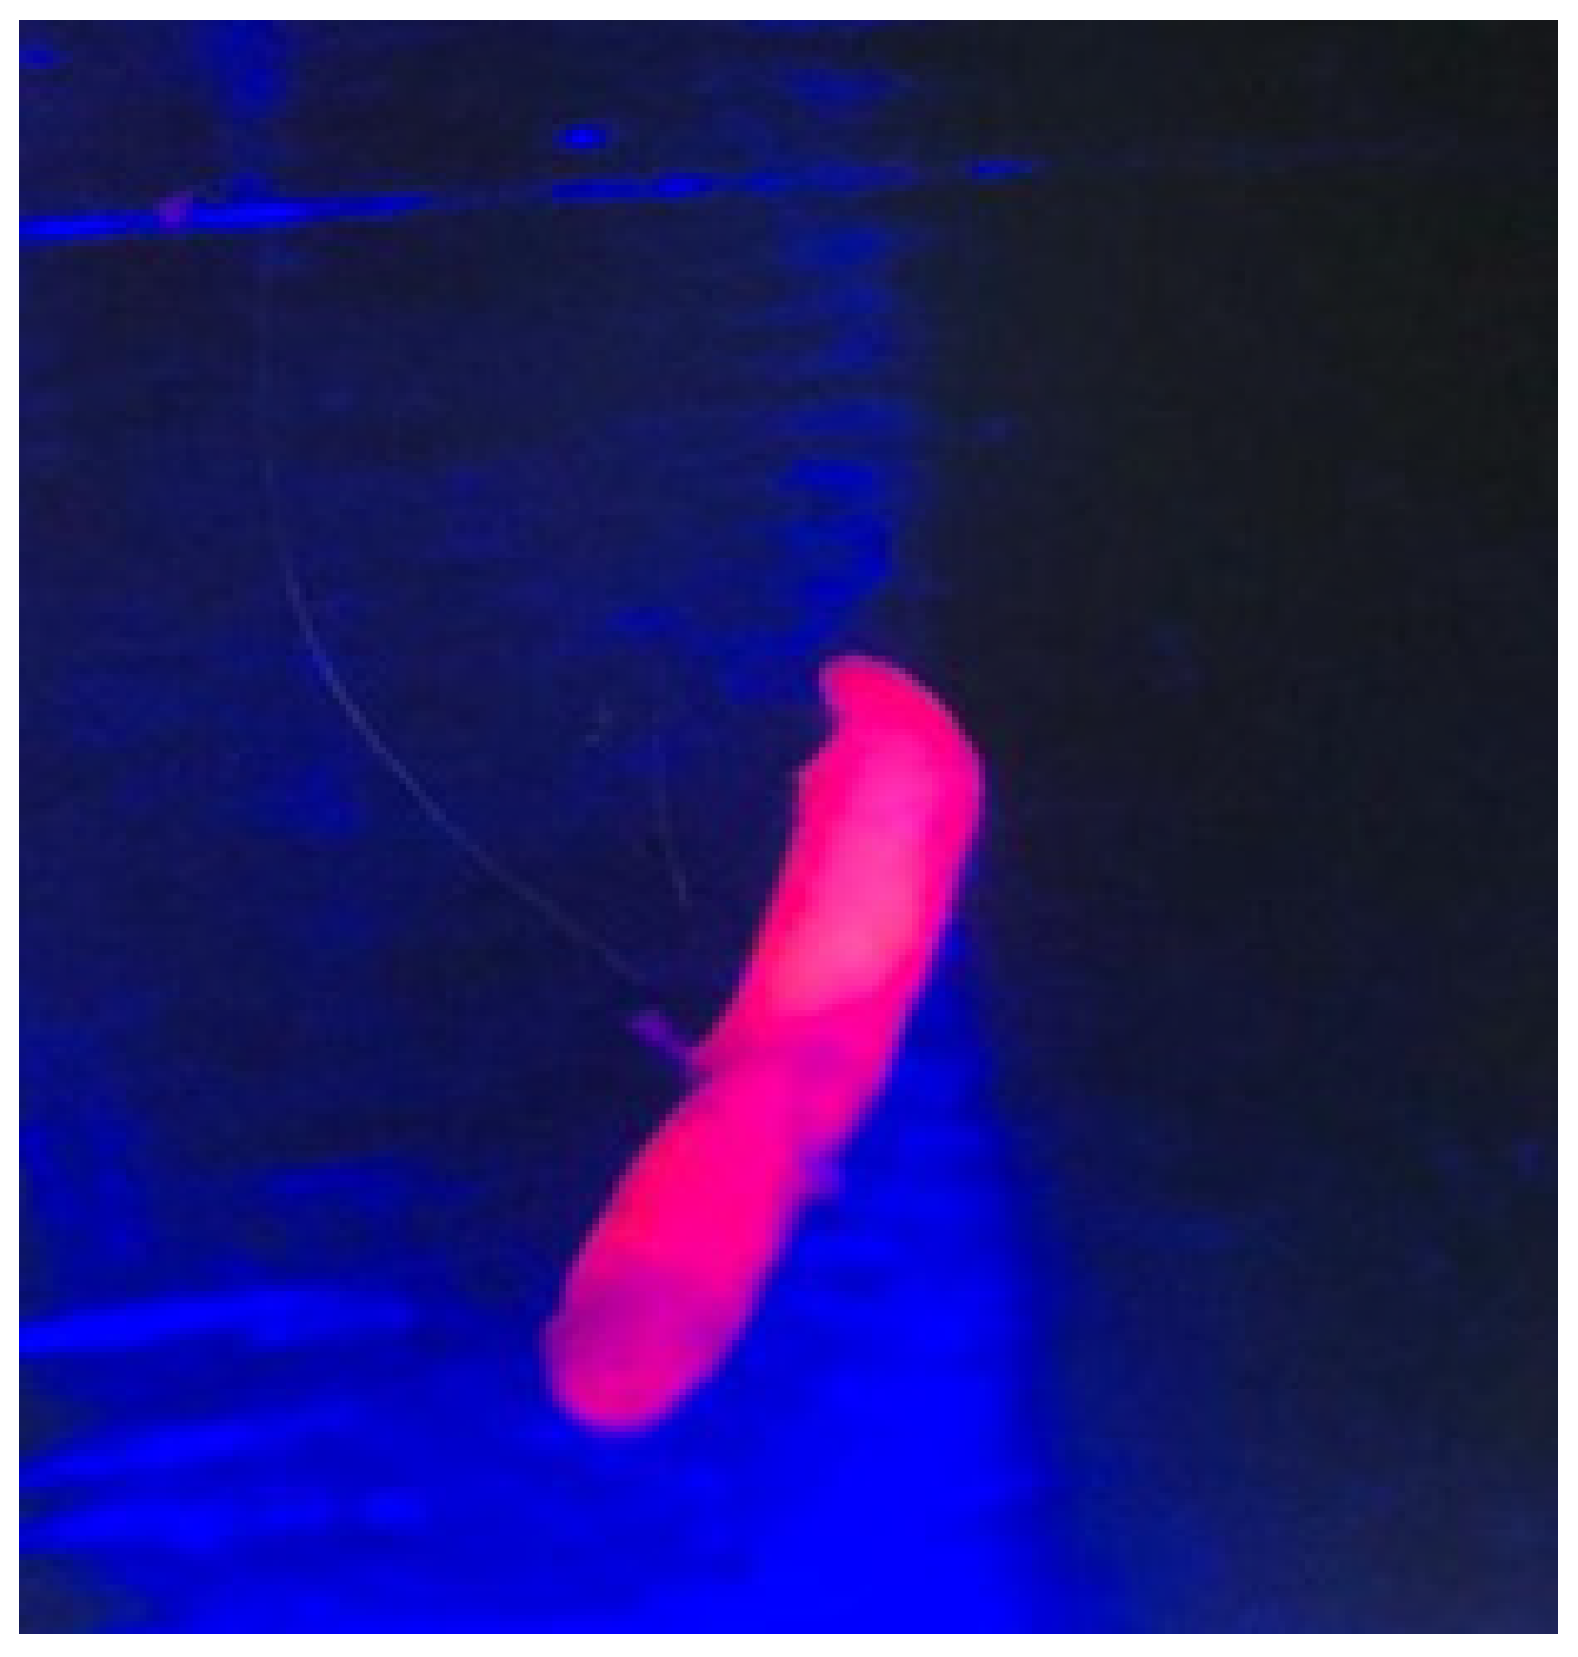

Figure 1.

Visualization of the red fluorescent sample under the light of the microscope to confirm the adequacy of the tissue.